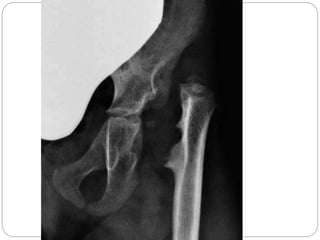

Detection of sequelae

 history, medical documentation, clinical

examination, radiographs, arthrography and

sonography.

 Head of femur- purely cartilaginous - more

susceptible to direct destructive activity of pus

& inflammatory products

 Increase in intracapsular pressure –

tamponade – AVN of head

 often diagnosed late- leading to irreversible

damage to the articular cartilage, blood supply to

the epiphysis

 absorption of head and neck,

 resulting in severe shortening and disability.